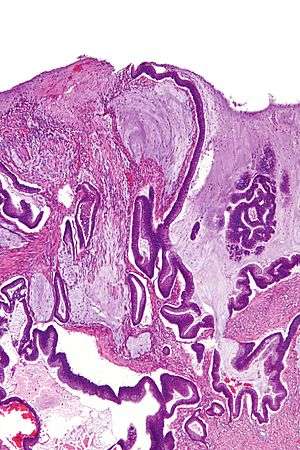

| Micrograph of a mucinous adenocarcinoma of the colon. H&E stain. | |

Mucinous carcinoma is a type of cancer that arises from epithelial cells; these line certain internal organs and skin, and produce mucin (the main component of mucus).